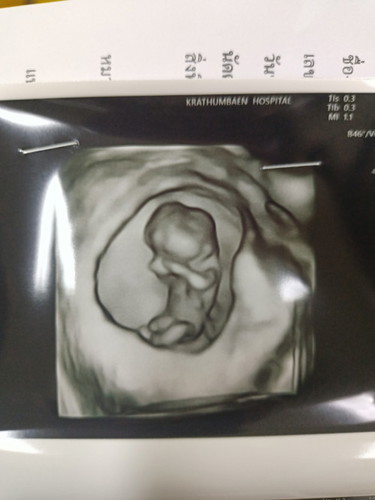

ของแม่ๆน้องอยู่ท่าไหนกันบ้างคะ บ้านนี้หมอซาวด์ทั้งแบบปกติ และ4มิติให้ค่ะ แต่น้องเอามือปิดหน้าไม่ให้เห็นเลยค่ะ